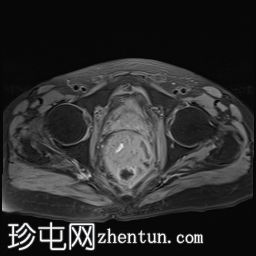

矢状位

T2加权像

直肠下三分之一处可见一段弥漫性不规则肠壁增厚,伴浆膜外延伸,在右前外侧壁形成“C”形肿块,增强后呈不均匀强化,中央可见坏死。

左侧外侧壁和后壁可见大片缺损,内含气体和粪便,被不规则增厚的肠壁包裹。该缺损在T1加权像上呈低信号,在T2加权像上呈高信号,并伴有明显的扩散受限。

可见肠系膜脂肪间隙条索状改变和水肿。